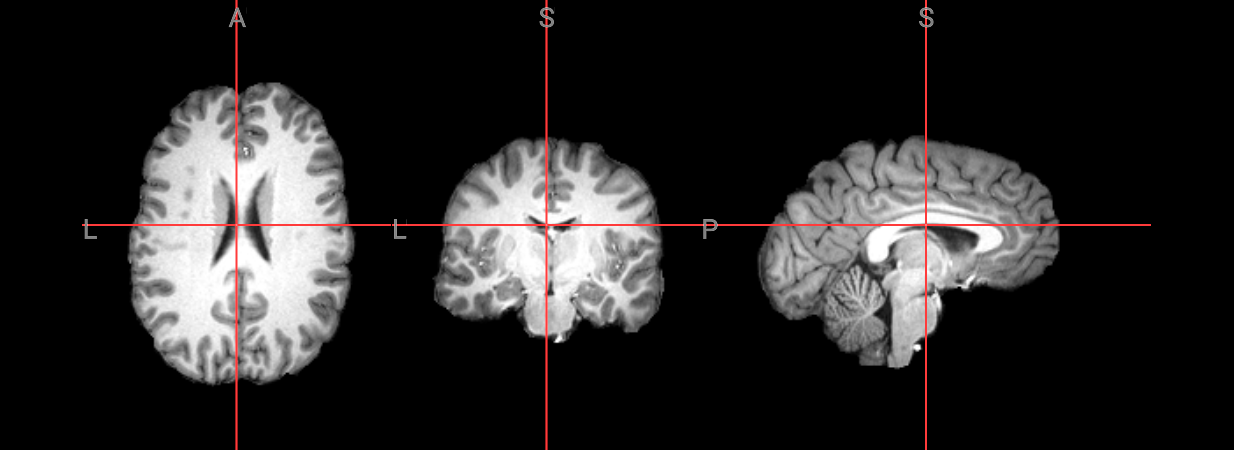

Since fMRI studies focus on brain tissue, our first step is to remove the skull and non-brain areas from the image.

In order to analyze fMRI data, you will need to load an fMRI analysis package. In this example we will use the following packages and algorithms to skull-strip the anatomical image:

Advanced Normalization Tools (ANTs): antsBrainExtraction.sh

Analysis of Functional NeuroImages (AFNI): 3dSkullStrip

FreeSurfer: SynthStrip

FSL (FMRIB Software Library, created by the University of Oxford): BET - Brain Extraction Tool